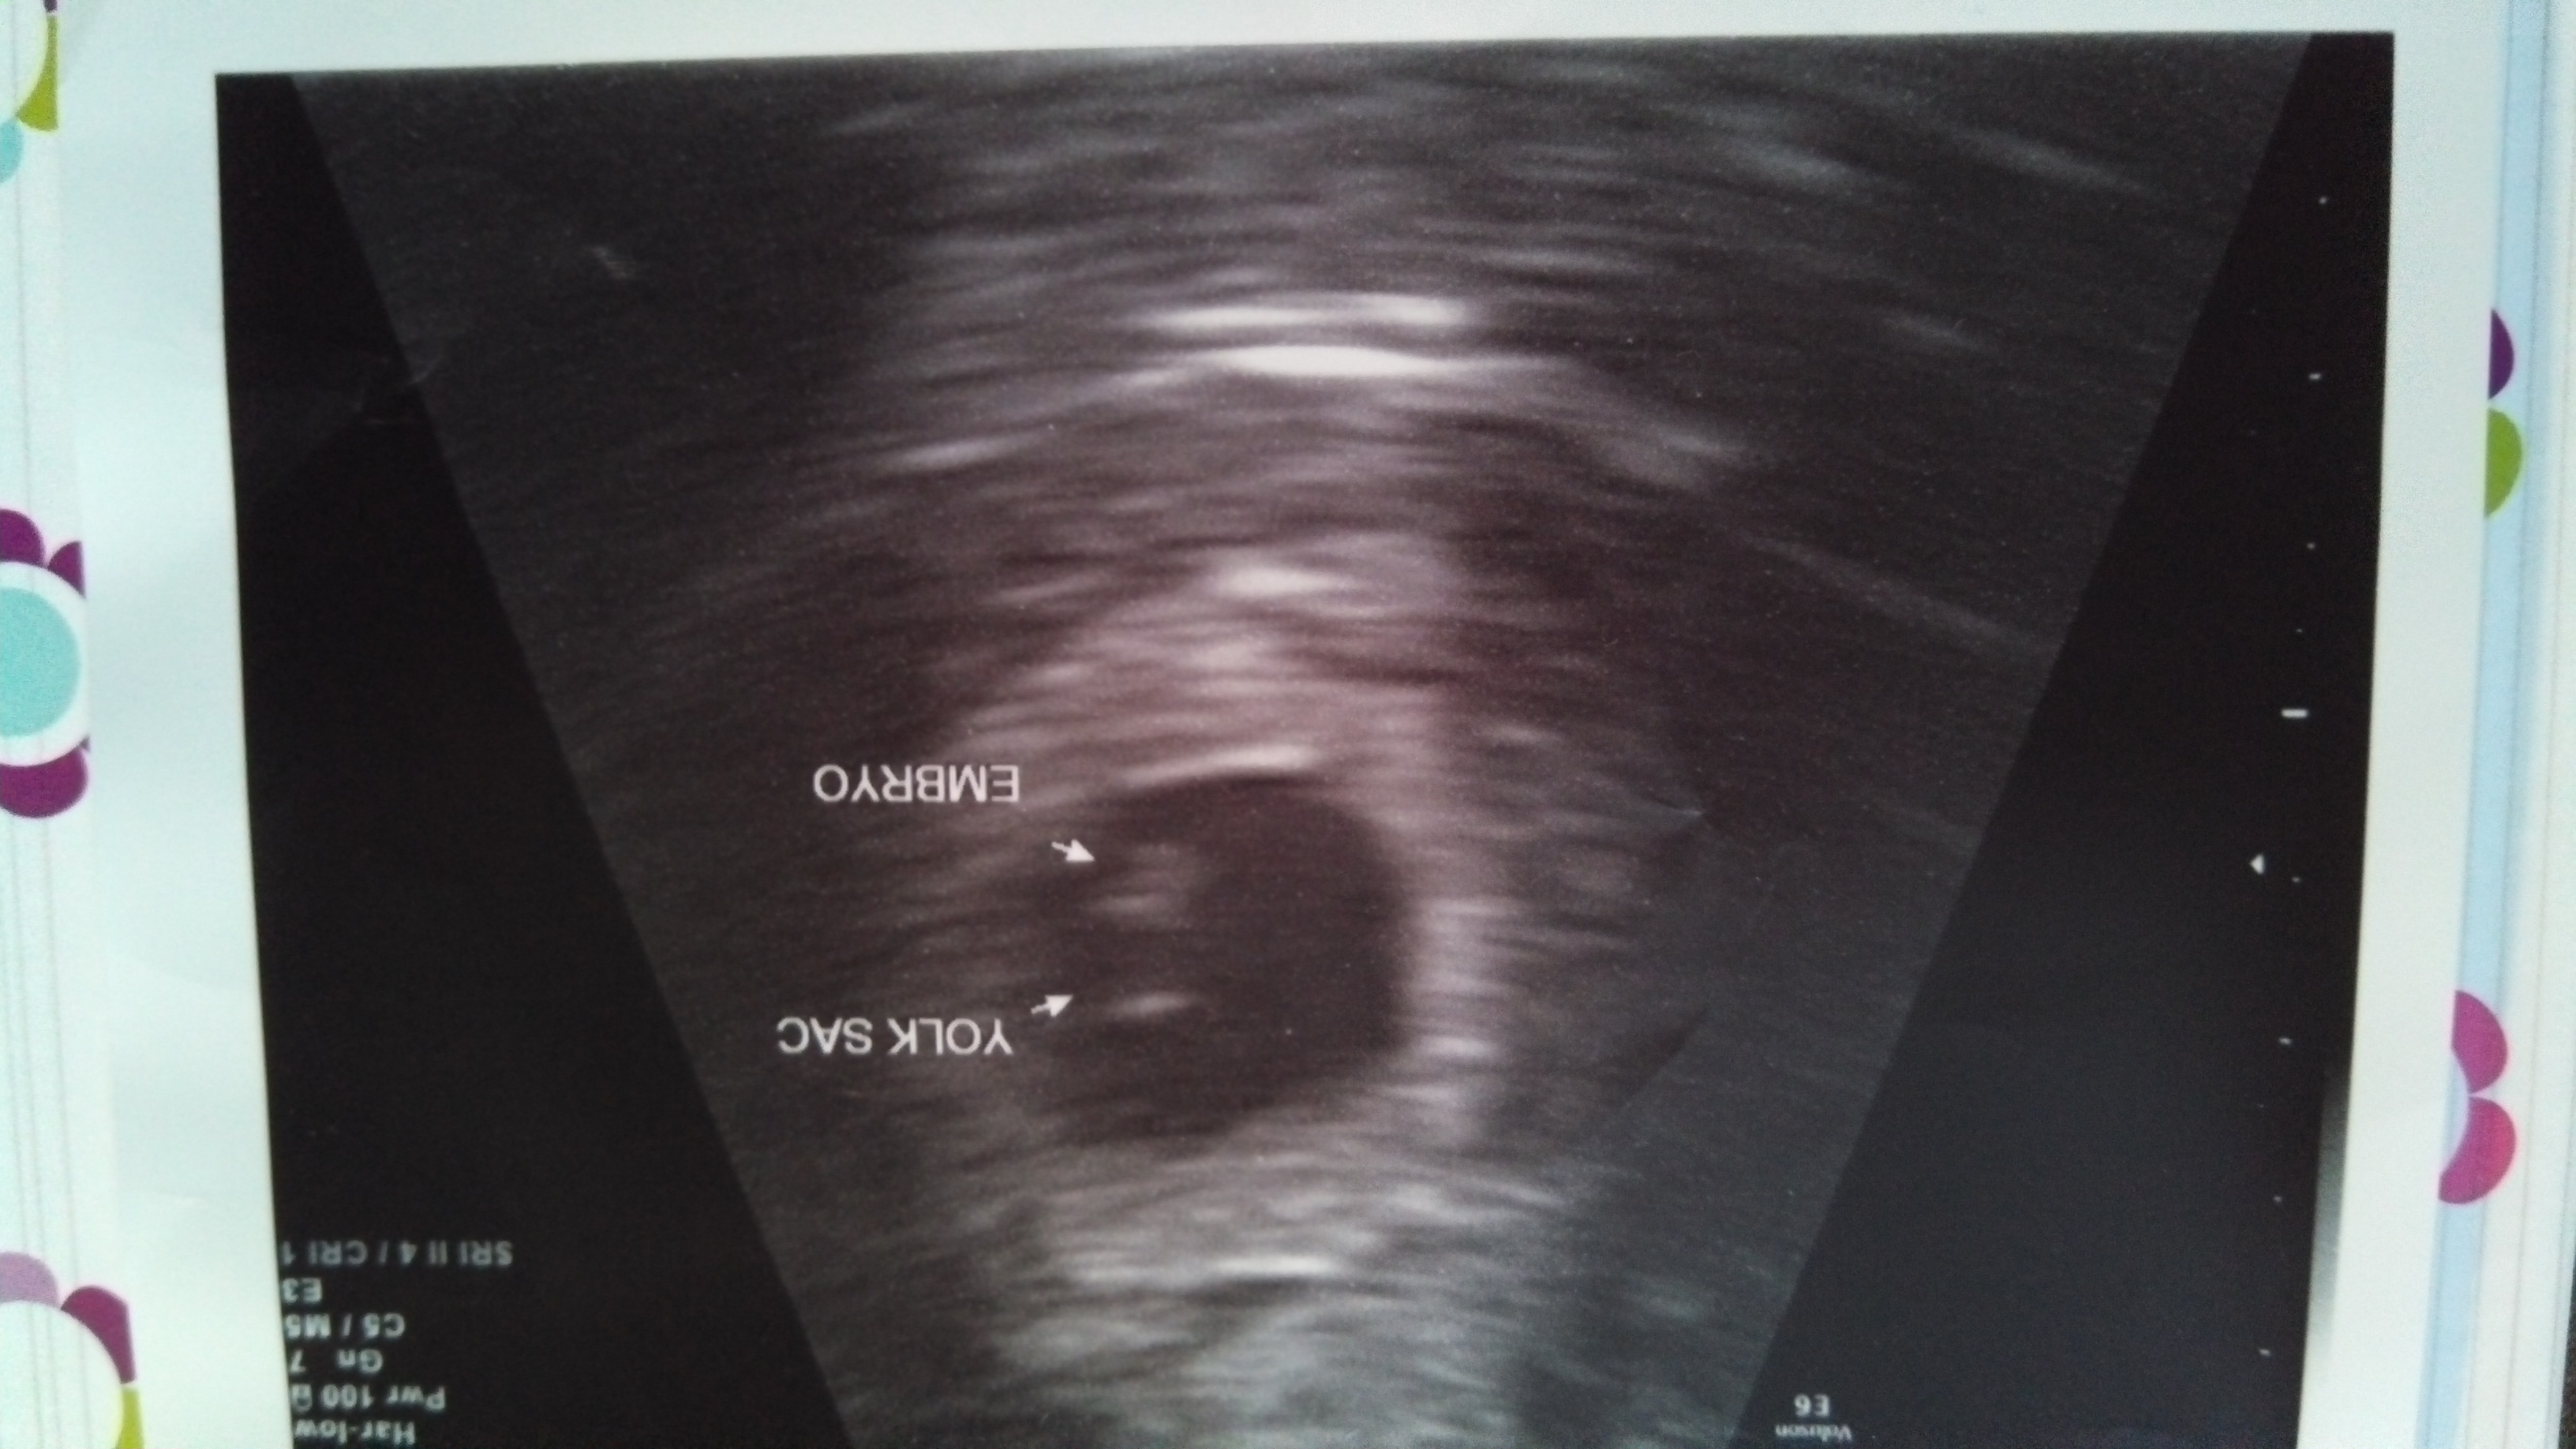

I am only 6 weeks and had my first appointment scheduled for next Monday.  Last night I felt a few sharp pains, so I emailed my doctor.  The doctor's office just called and wanted to know if I could come on in today for an US and meet with the doctor afterwards.  Please pray that everything is developing normally and that those pains did not mean anything.  Thank you!  I believe in prayers and appreciate anyone that can pray for my 2:30 US.

• Awesome, I'm so glad everything went well! Adorable bean!